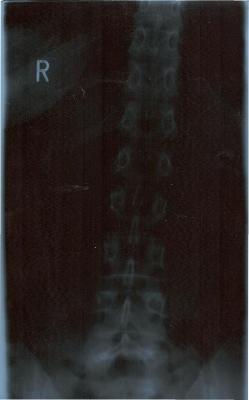

Ach so bevor ich vergesse: von meinem Rücken bestehen 4 Röbis, die den gesamten Rücken zeigen. Das Bild von der LWS ist eigenartig: erst unten gerade und dann geht sie schräg nach rechts hoch. Meine Orhopädin meint, die LWS sei kerzengerade, der FA aus Bochum meint, da hätte ich beim der Aufnahme einen Druck von links bekommen (ich stand aber allein und - für mich - gerade vor dem Gerät. Mich hat nichts und niemand gedrückt - interessiert die Ärzte aber nicht). Leider konnte ich dem Menschen in Bochum auch nur die zeigen, da die CD`s noch im Krankenhaus unterwegs sind.

Die Röntgenbilder habe ich nochmal reingestellt. Sorry, das mit dem Bild verkleinern wusste ich nicht. Ich hab die Bilder zwar in der falschen Reihenfolge eingestellt, aber ich hoffe, dass das nicht tragisch ist: zuerst also das untere Bild (mit Becken), dann das obere für den weiteren Verlauf. Alles wieder im Testforum!

Zum zum Röbi an sich: Es ist wirklich komisch, wie schief das nach oben geht. Ich vermute daher, dass deine eigentliche Krümmung darüber, also in der BWS sitzt oder du eine langgezogene Krümmung hast, die in der BWS weitergeht und dann wieder zur Mitte geht. Aber genau deshalb braucht man eine Ganzwirbelsäulen-Aufnahme!!

ich wollte erst schauen, ob das mit den Bildern funktionert - daher Testforum. Der erste Versuch ist ja auch schief gegangen, doch im Testforum problemlos löschbar. Jetzt hat es geklappt, daher habe ich sie jetzt auch hier. So können sich auch andere dazu äußern (obwohl Deine Meinung schon sehr fachfraulich klingt und ich fast glaube, dass mein Schicksal besiegelt ist!!!). Jedenfalls tut es mir gut, dass jemand anderes auch meint, dass meine WS eben doch nicht kerzengerade aussieht - ich freue mich (dachte nämlich schon, ich wäre bekloppt).

es wäre wirklich interessant, wie deine Wirbelsäule im Ganzen aussieht. In der LWS hast du zumindest schonmal keine Rotation, was positiv ist. Evtl. ist es ja nur eine Fehlhaltung oder eben eine typische Begleit-Skoliose bei Rundrücken. Deshalb ist auch ein seitliches Röntgenbild zur Diagnostik notwendig.Jedenfalls tut es mir gut, dass jemand anderes auch meint, dass meine WS eben doch nicht kerzengerade aussieht - ich freue mich (dachte nämlich schon, ich wäre bekloppt).